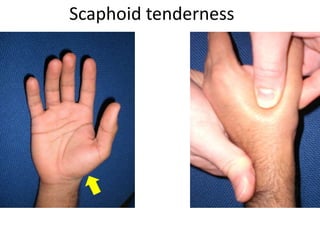

- Naming the bones, joints, tendons, nerves and skin landmarks of the hand and wrist.